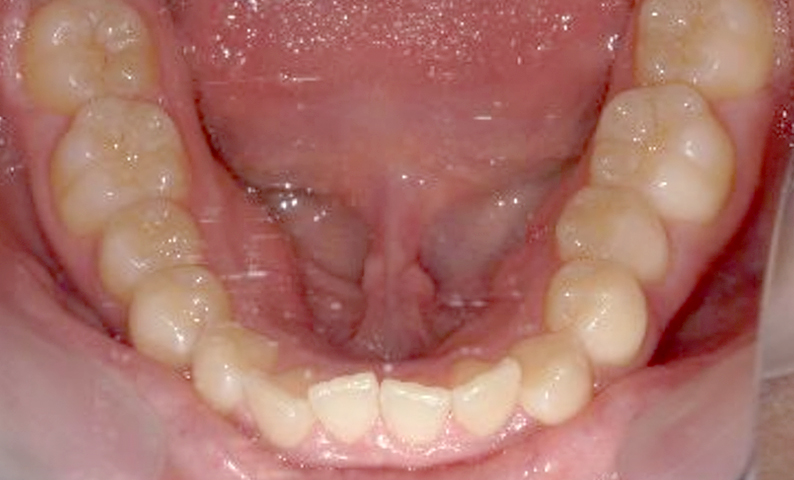

症例:上下顎の部分矯正

症例_002 前歯「捻転歯」症例

治療期間:10ヶ月金額:54万円+税30代女性少しのねじれ捻転歯前歯の突出感